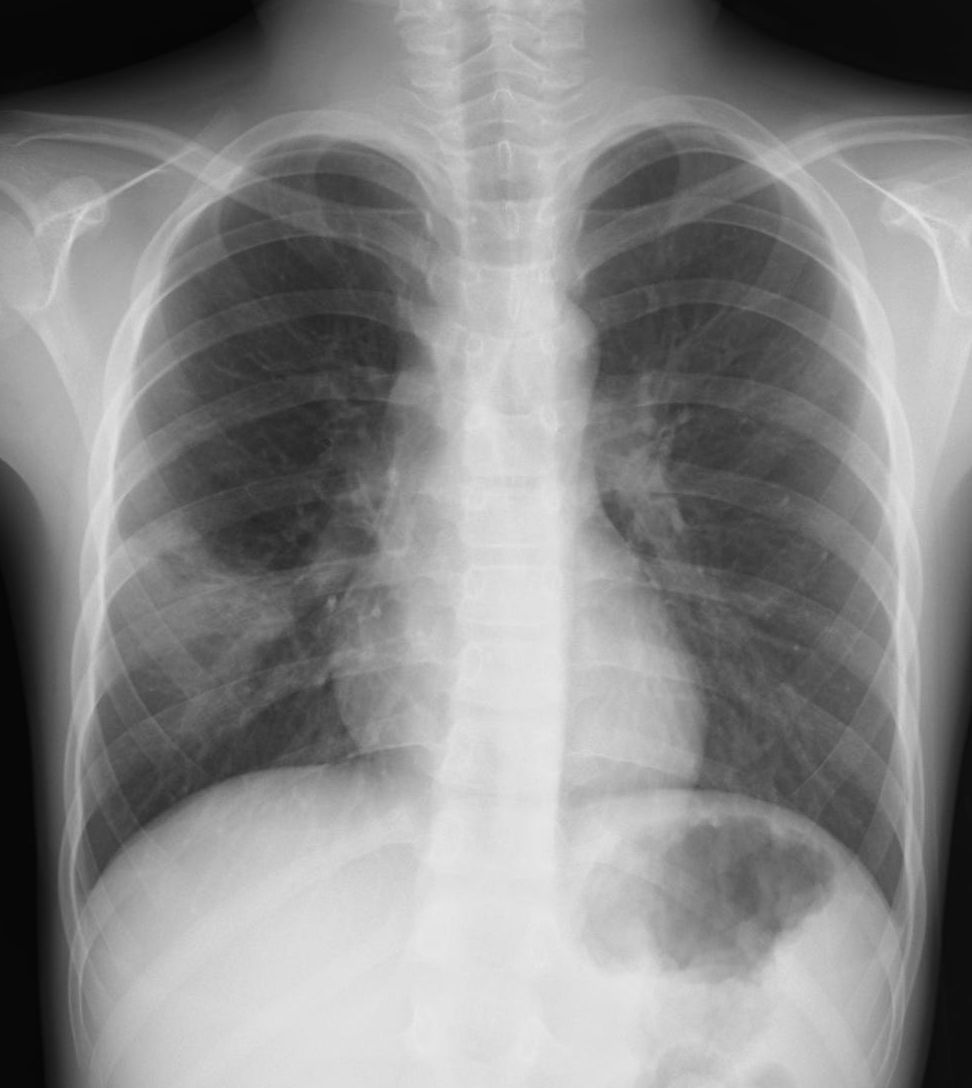

外来でよくみられる肺炎、マイコ・クラミジア・肺炎球菌・ウイルス(RSウイルス・hMPV・インフルエンザウイルスA・B)について実際に経験、外来で治癒した症例を提示します。軽症な変化のものが大多数ですが中には重症なものも紛れていて、注意が必要になります。

【マイコプラズマ肺炎】